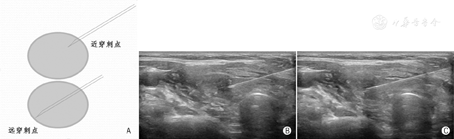

在目标结节内针尖须作较大幅度来回提插移动,最理想的幅度是从目标结节的近穿刺点达其远穿刺点(图16),以获取穿刺针道上最大量的标本。

在目标结节内针尖近似原地快速、小幅度"颤动式"提插是不合适、不可取的操作方式(图17)。取材结束时,穿刺针退出结节时的速度亦不宜过快。